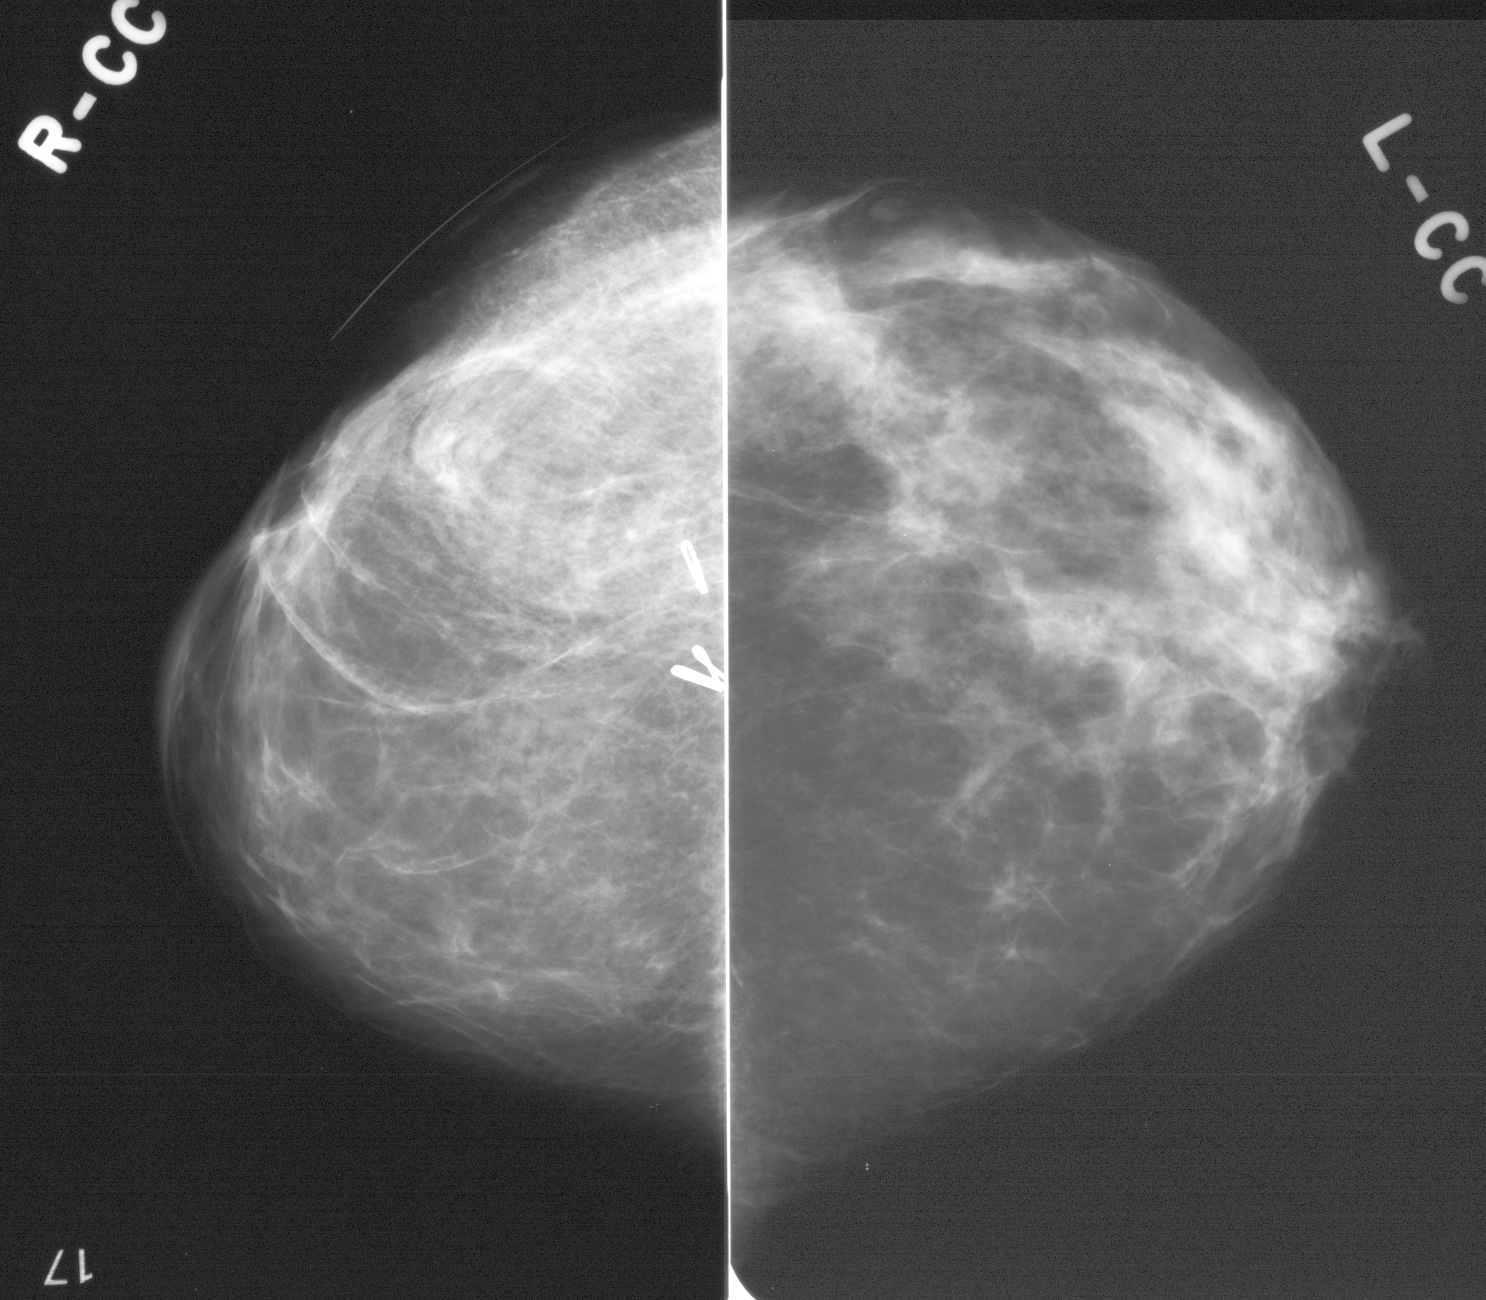

◂Breast Anatomy